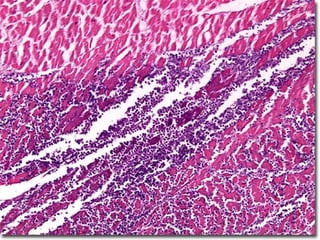

Heart, coagulative necrosis

(myocardial infarct) - Gross, cross section

Heart, acute myocardial infarct - High power

Heart, coagulative necrosis (myocardialinfarct) - Gross, cross section

Heart, acute myocardialinfarct - High power